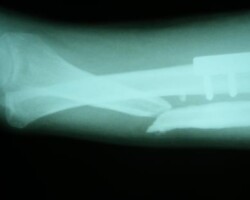

Αγγειούμενη περόνη

Άντρας 21 ετών υπέστη διπολικό κάταγμα της κερκίδας και κάταγμα της ωλένης, που αντιμετωπίστηκε σε περιφεριακό νοσοκομείο. 9 μήνες μετά διαπιστώθηκε ψευδάρθρωση της κερκίδας με οστικό απόλυμα 6,5 εκ. Αντιμετωπίστηκε με τη χρήση αγγειούμενης περόνης, η οποία γεφύρωσε το οστικό έλλειμμα της κερκίδας.